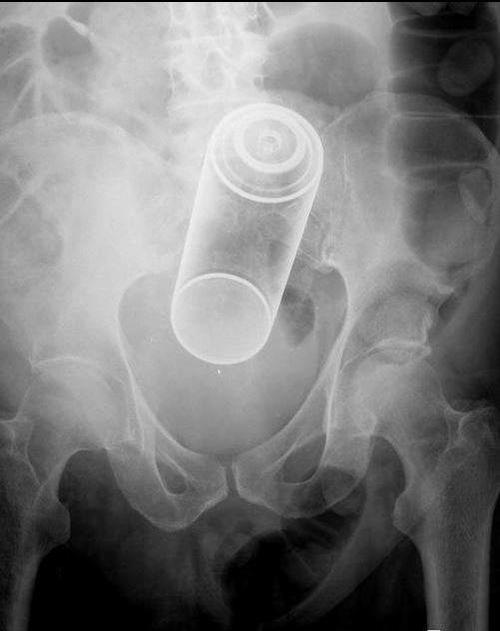

Una mención especial merece la colección de radiografías correspondientes a elementos extraños insertados voluntariamente en el cuerpo, como botes de desodorante, botellas de bebida energética, frutas y verduras o hasta un huevo son algunos de los casos que los autores de la Radiopaedia han compartido.

Una vez la berengena ingresó en el cuerpo de esta persona, no hubo forma de recuperarla. El avergonzado personaje tuvo que presentarse en el hospital para resolver su problema.